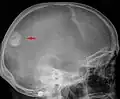

Meningeom im Röntgenbild des Schädels -

Das bildgebende Verfahren der ersten Wahl ist beim Meningeom heute die Kernspintomografie, da dieses Verfahren den größten Weichteilkontrast besitzt und in typischen Fällen die sichere Diagnose eines Meningeoms ermöglicht. In T2-gewichteten Aufnahmen stellen sich verkalkte Meningeome im Gegensatz zu vielen anderen Tumoren als schwarze Masse (hypointens) dar, die dunkler als das umgebende Hirngewebe ist. Unverkalkte Meningeome können zur Umgebung isointens sein. Von anderen Tumoren unterscheiden sich Meningeome durch ihre Lage auf der Dura mater mit charakteristischen Ausläufern in die Dura (dural tails) und durch eine sehr intensive Kontrastmittelaufnahme. Die Computertomographie kann die Tumorverkalkungen sehr gut nachweisen. Konventionelles Röntgen und Angiographie haben heute nur noch eine untergeordnete Bedeutung.